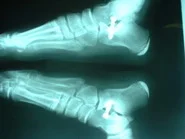

Caso clínico: Paciente de 10 años de edad, quien presentaba pie plano valgo doloroso, con acortamiento del tendón de Aquiles (gemelos). Fue intervenido quirúrgicamente practicándose  cura operatoria según la técnica de calcáneo stop, con la colocación de tornillo de bloqueo en el seno del tarso y alargamiento del tendón de Aquiles según técnica de Vulpius. Excelente resultado postoperatorio. Ver imágeness arriba y a la derecha.

Postoperatorio. Vista posterio del pie.